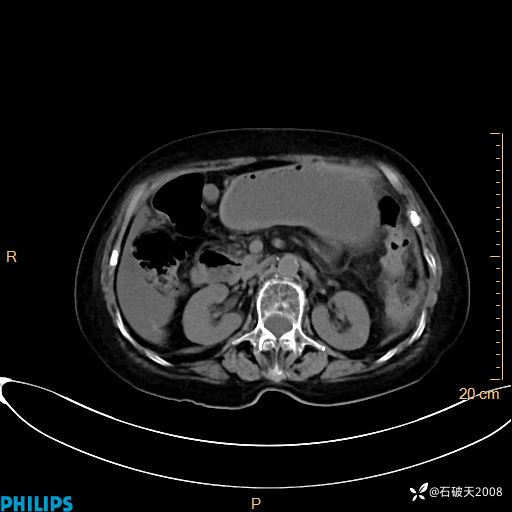

MIP